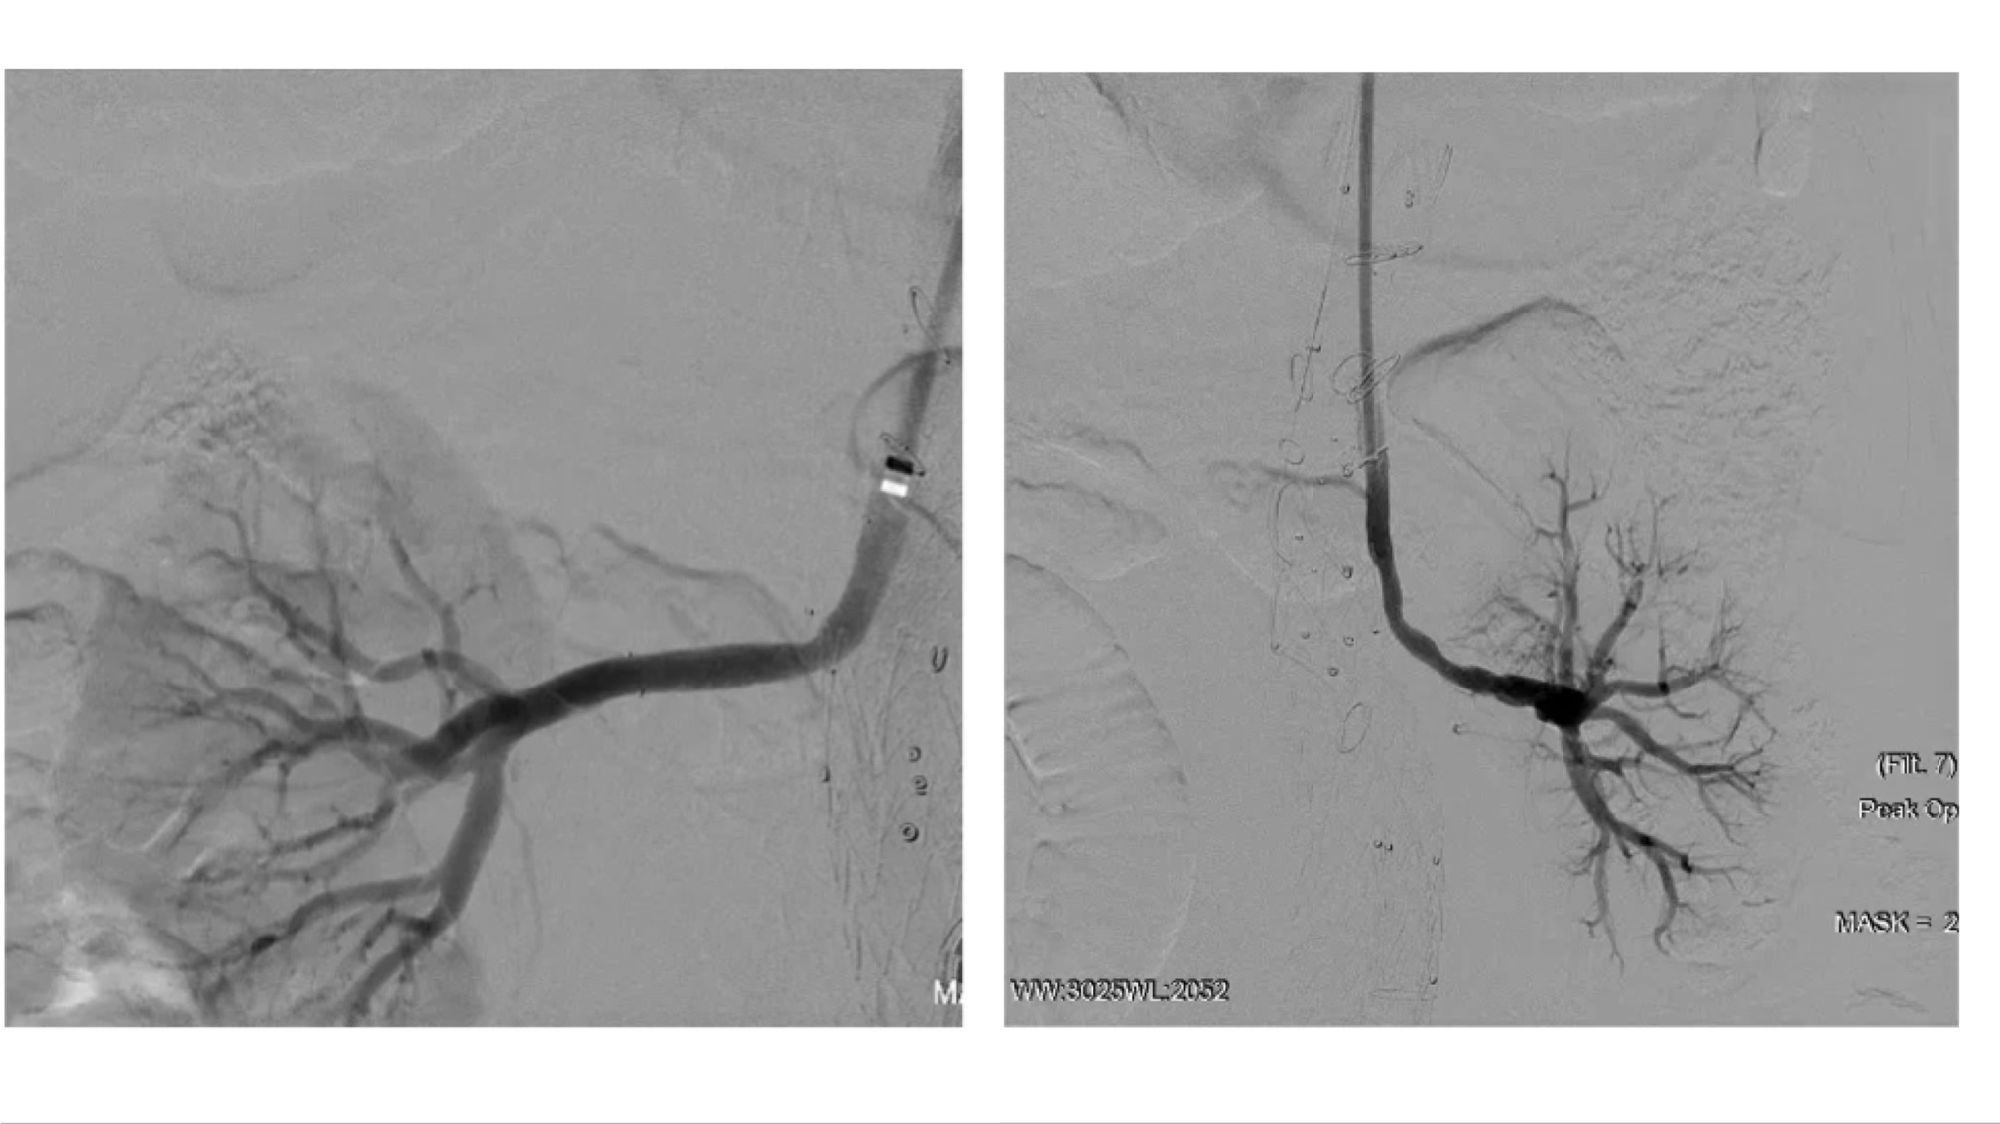

腔内重建右肾和左肾动脉

(右肾开口处重度狭窄,左肾烟囱支架术后增加了手术难度)

术后造影及出院前随访:

患者胸腹主动脉瘤隔绝完全,支架位置及形态良好,各分支动脉重建后血流通畅,无内漏发生。